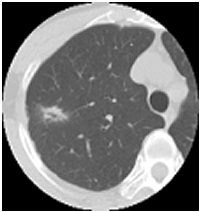

マルチスライスCT画像 |

←左はマルチスライスCTで撮った断層写真です。直径約2cmの肺癌の腫瘍陰影がはっきり写っています。

このように一般の単純写真では、専門の放射線の医師でも判定が不可能な異常がマルチスライスCTでははっきり撮すことが出来ます。